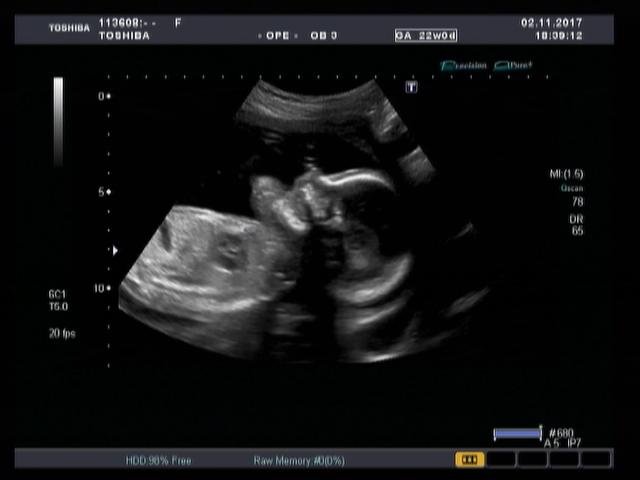

Precision Imaging (Прецизионная визуализация) ультразвуковой системы Aplio позволяют получать более реалистичные изображения и обеспечивает высокую степень послойной дифференцировки тканевых структур и анатомическую точность в визуализации деталей.

Режим дифференцированной тканевой гармоники (DTH) обеспечивает высокую детализацию глубоко расположенных структур. Поскольку в этом режиме за один импульс передаются сигналы на двух различных частотах, изображения обладают непревзойденным пространственным разрешением и контрастностью, а также большей глубиной проникновения.

Функция автоматического измерения толщины воротникового пространства (Auto NT measurement) представляет собой инструмент для оценки размера воротниковой зоны плода, обеспечивающий превосходную воспроизводимость результатов. Эта функция позволяет проводить автоматические измерения и получать достоверные и воспроизводимые результаты при недостаточно четкой визуализации.